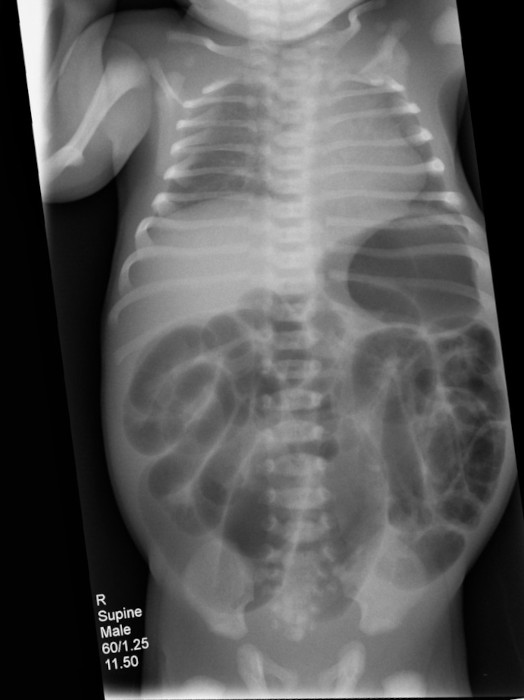

Tratto da Wikipedia ingleseLa malattia di Hirschsprung è un disturbo presente già alla nascita per cui l'innervazione dell'intestino manca di alcune componenti. Il sintomo più importante è la stitichezza. Altri sintomi possono includere vomito, dolore addominale, diarrea e lento accrescimento. I sintomi di solito diventano evidenti nei primi due mesi di vita.

Purtroppo le complicazioni possono includere enterocolite, megacolon (il colon assume dimensioni ragguardevoli), occlusione intestinale e perforazione intestinale (per necrosi della parete intestinale).